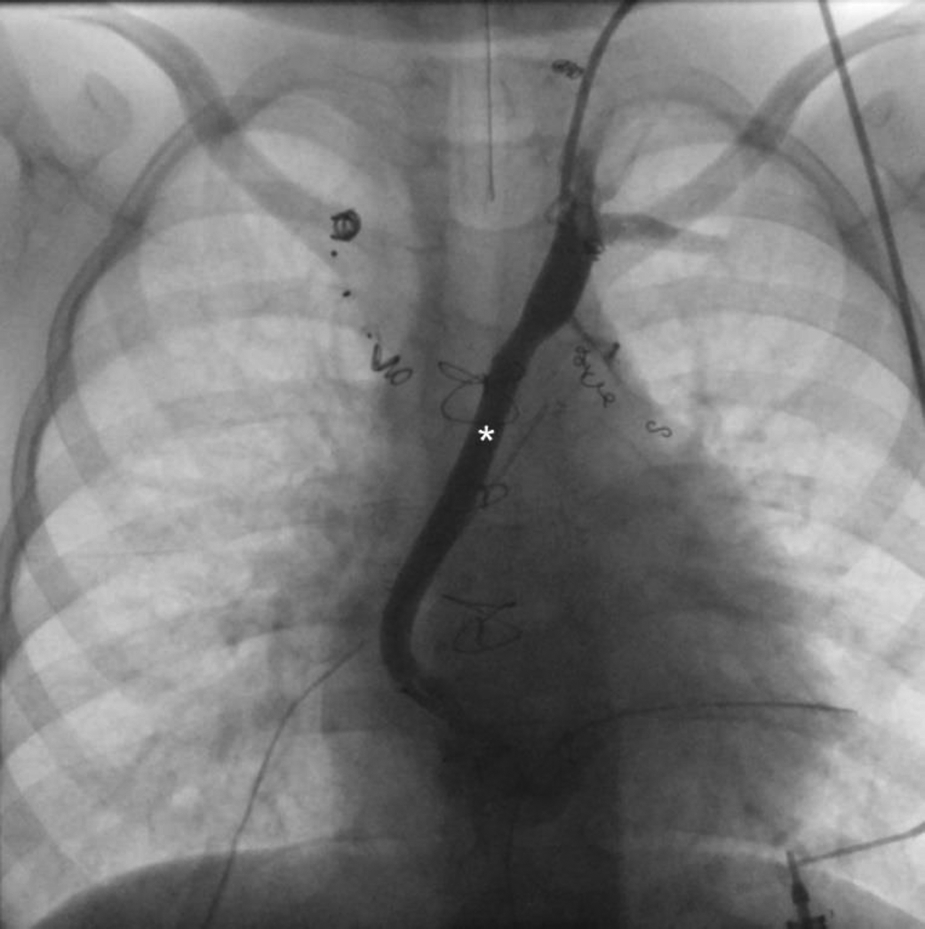

Figure 12

Ap fluoroscopic imaging of a 5 year old patient after surgical TD decompression demonstrating an unobstructed shunt (asterixis) between the innominate vein and the atrium. TD, thoracic duct.